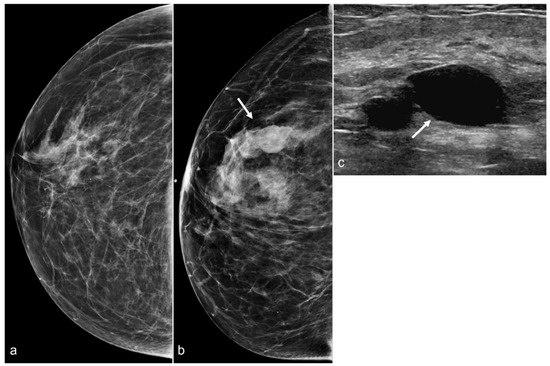

Asymmetries and masses anterior to the pectoralis major muscle are common findings following BES. These findings are often seen in patients with a history of subglandular implants. Post-surgical findings with focal linear asymmetries are usually secondary to fibrosis (Figure 7). Hematomas and seromas may be seen on mammography as large dense masses (Figure 8). Ultrasound is helpful in showing the typical features of hematomas and seromas (Figure 9). Developing masses in patients who are status post BES should be carefully evaluated with mammography and ultrasound. Figure 10 shows developing masses in the region of the BES scar. A subsequent ultrasound showed cysts.

Figure 8. A 67-year-old woman with subglandular silicone implants developed a large, dense right subglandular mass (arrow) on mammography (a) two years after BES. Follow-up longitudinal right breast ultrasound (b) demonstrates a fluid collection with internal debris, confirming evidence of a seroma.

Figure 10. A 58-year-old woman with a history of BIA-ALCL and subsequent BES of retropectoral silicone implants. Post-BES CC mammogram (a) and most recent mammogram CC view (b) demonstrate developing masses (arrow). Right breast ultrasound in the transverse view (c) shows cysts (arrow).